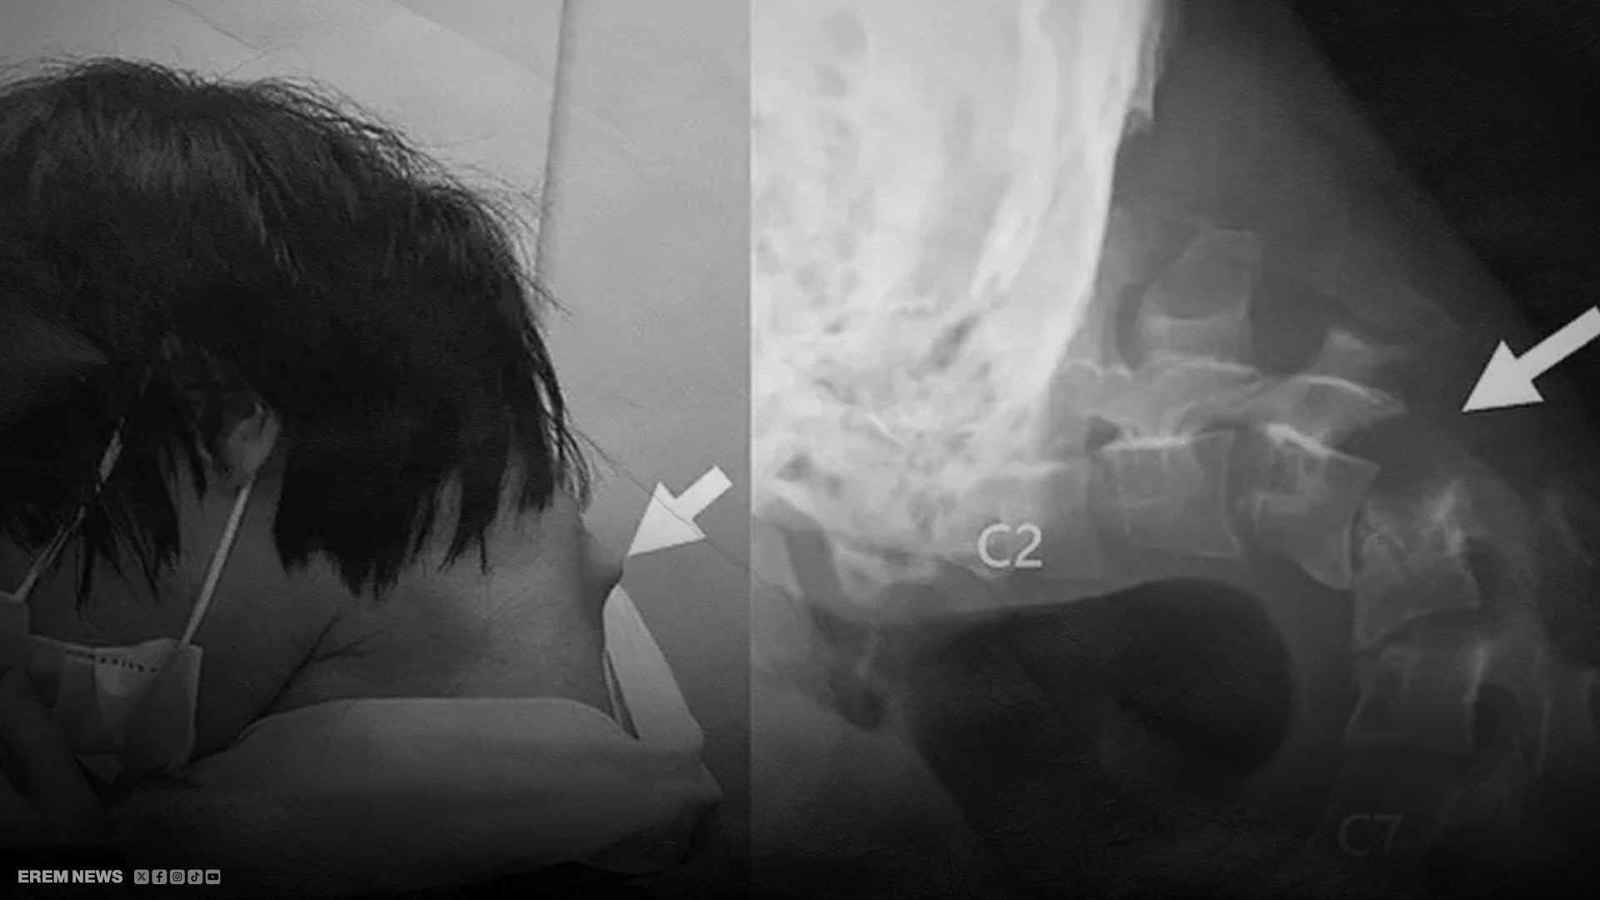

مع مرور الوقت، بدأ يشعر بآلام شديدة في رقبته وقد تفاقمت حالته حتى أصبح غير قادر على رفع رأسه بسبب ضعف فقرات رقبته حيث أظهرت صورة الأشعة تآكلًا كبيرًا في فقراته، مما أدى إلى تشوهها ونمو أنسجة تشبه الندبات حول العمود الفقري ورغم محاولات الأطباء استخدام أطواق طبية لدعمه، فإن المريض لم يتحملها بسبب التنميل الذي أصابه، ما دفعهم في النهاية لإجراء سلسلة من العمليات الجراحية المعقدة تم خلالها تثبيت رقبته باستخدام قضبان وبراغٍ طبية ليتمكن المريض من استعادة بعض قدراته وذلك بعد ستة أشهر، لكن رغم التحسن، فإن الحالة سترافقه طيلة حياته بحسب الأطباء..